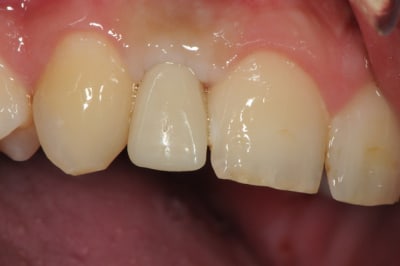

photos finish!!!

à noter...avec le flash...difficile de rendre le "naturel" de ces restaurations(teintes très claires)...après petite gingivoplastie pour harmoniser la hauteur des collets...(surtout pour 12...)